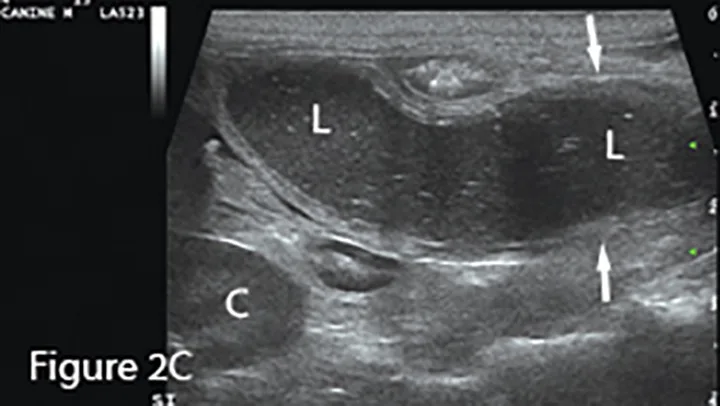

A longitudinal segment of severely fluid-distended small intestine (arrows) adjacent to normal bowel seen in transverse sections (*), suggesting obstruction. The greatly dilated lumen (L) shows speckled, echogenic fluid with readily observable movement in real-time examination. Potential cause (eg, foreign material, mass, intussusception) should be investigated. (K = caudal pole of kidney)